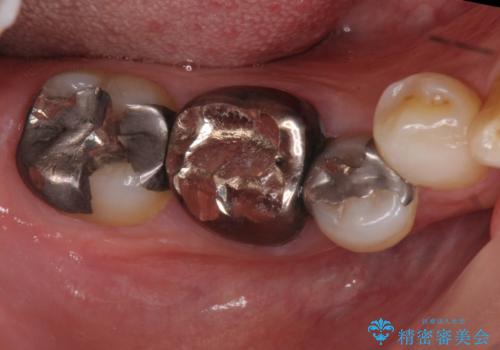

下の奥歯の虫歯 歯周外科手術を含めた治療

- 右下奥の銀歯の下が虫歯になっていました。

歯ぐきの下までしっかり修復するために、歯周外科手術を含めた治療を行いました。

⑴虫歯除去し、仮歯とする